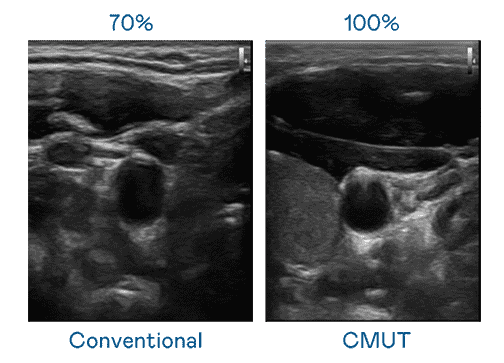

CMUT 技术是一种用电容式微机电元件来产生超音波讯号的技术。。。与传统 PZT 压电式技术相比,,CMUT 频宽增加 30%,,,更宽频的超音波讯号让影像解析度大幅提升,,,是实现高影像品质医疗超音波扫描、、、、促进精准医疗发展的关键技术。。。。

大频宽带来超清晰影像

超音波影像的解析度高低,,,首先取决于探头能发出的讯号频宽。。尊龙z6 CMUT 可提供高清晰的超音波讯号,,,提供高频宽、、、高灵敏度、、、、影像纹理细节更高的超音波影像,,协助医护人员缩短影像判读时间及利用精准的医疗影像进行诊断。。。。